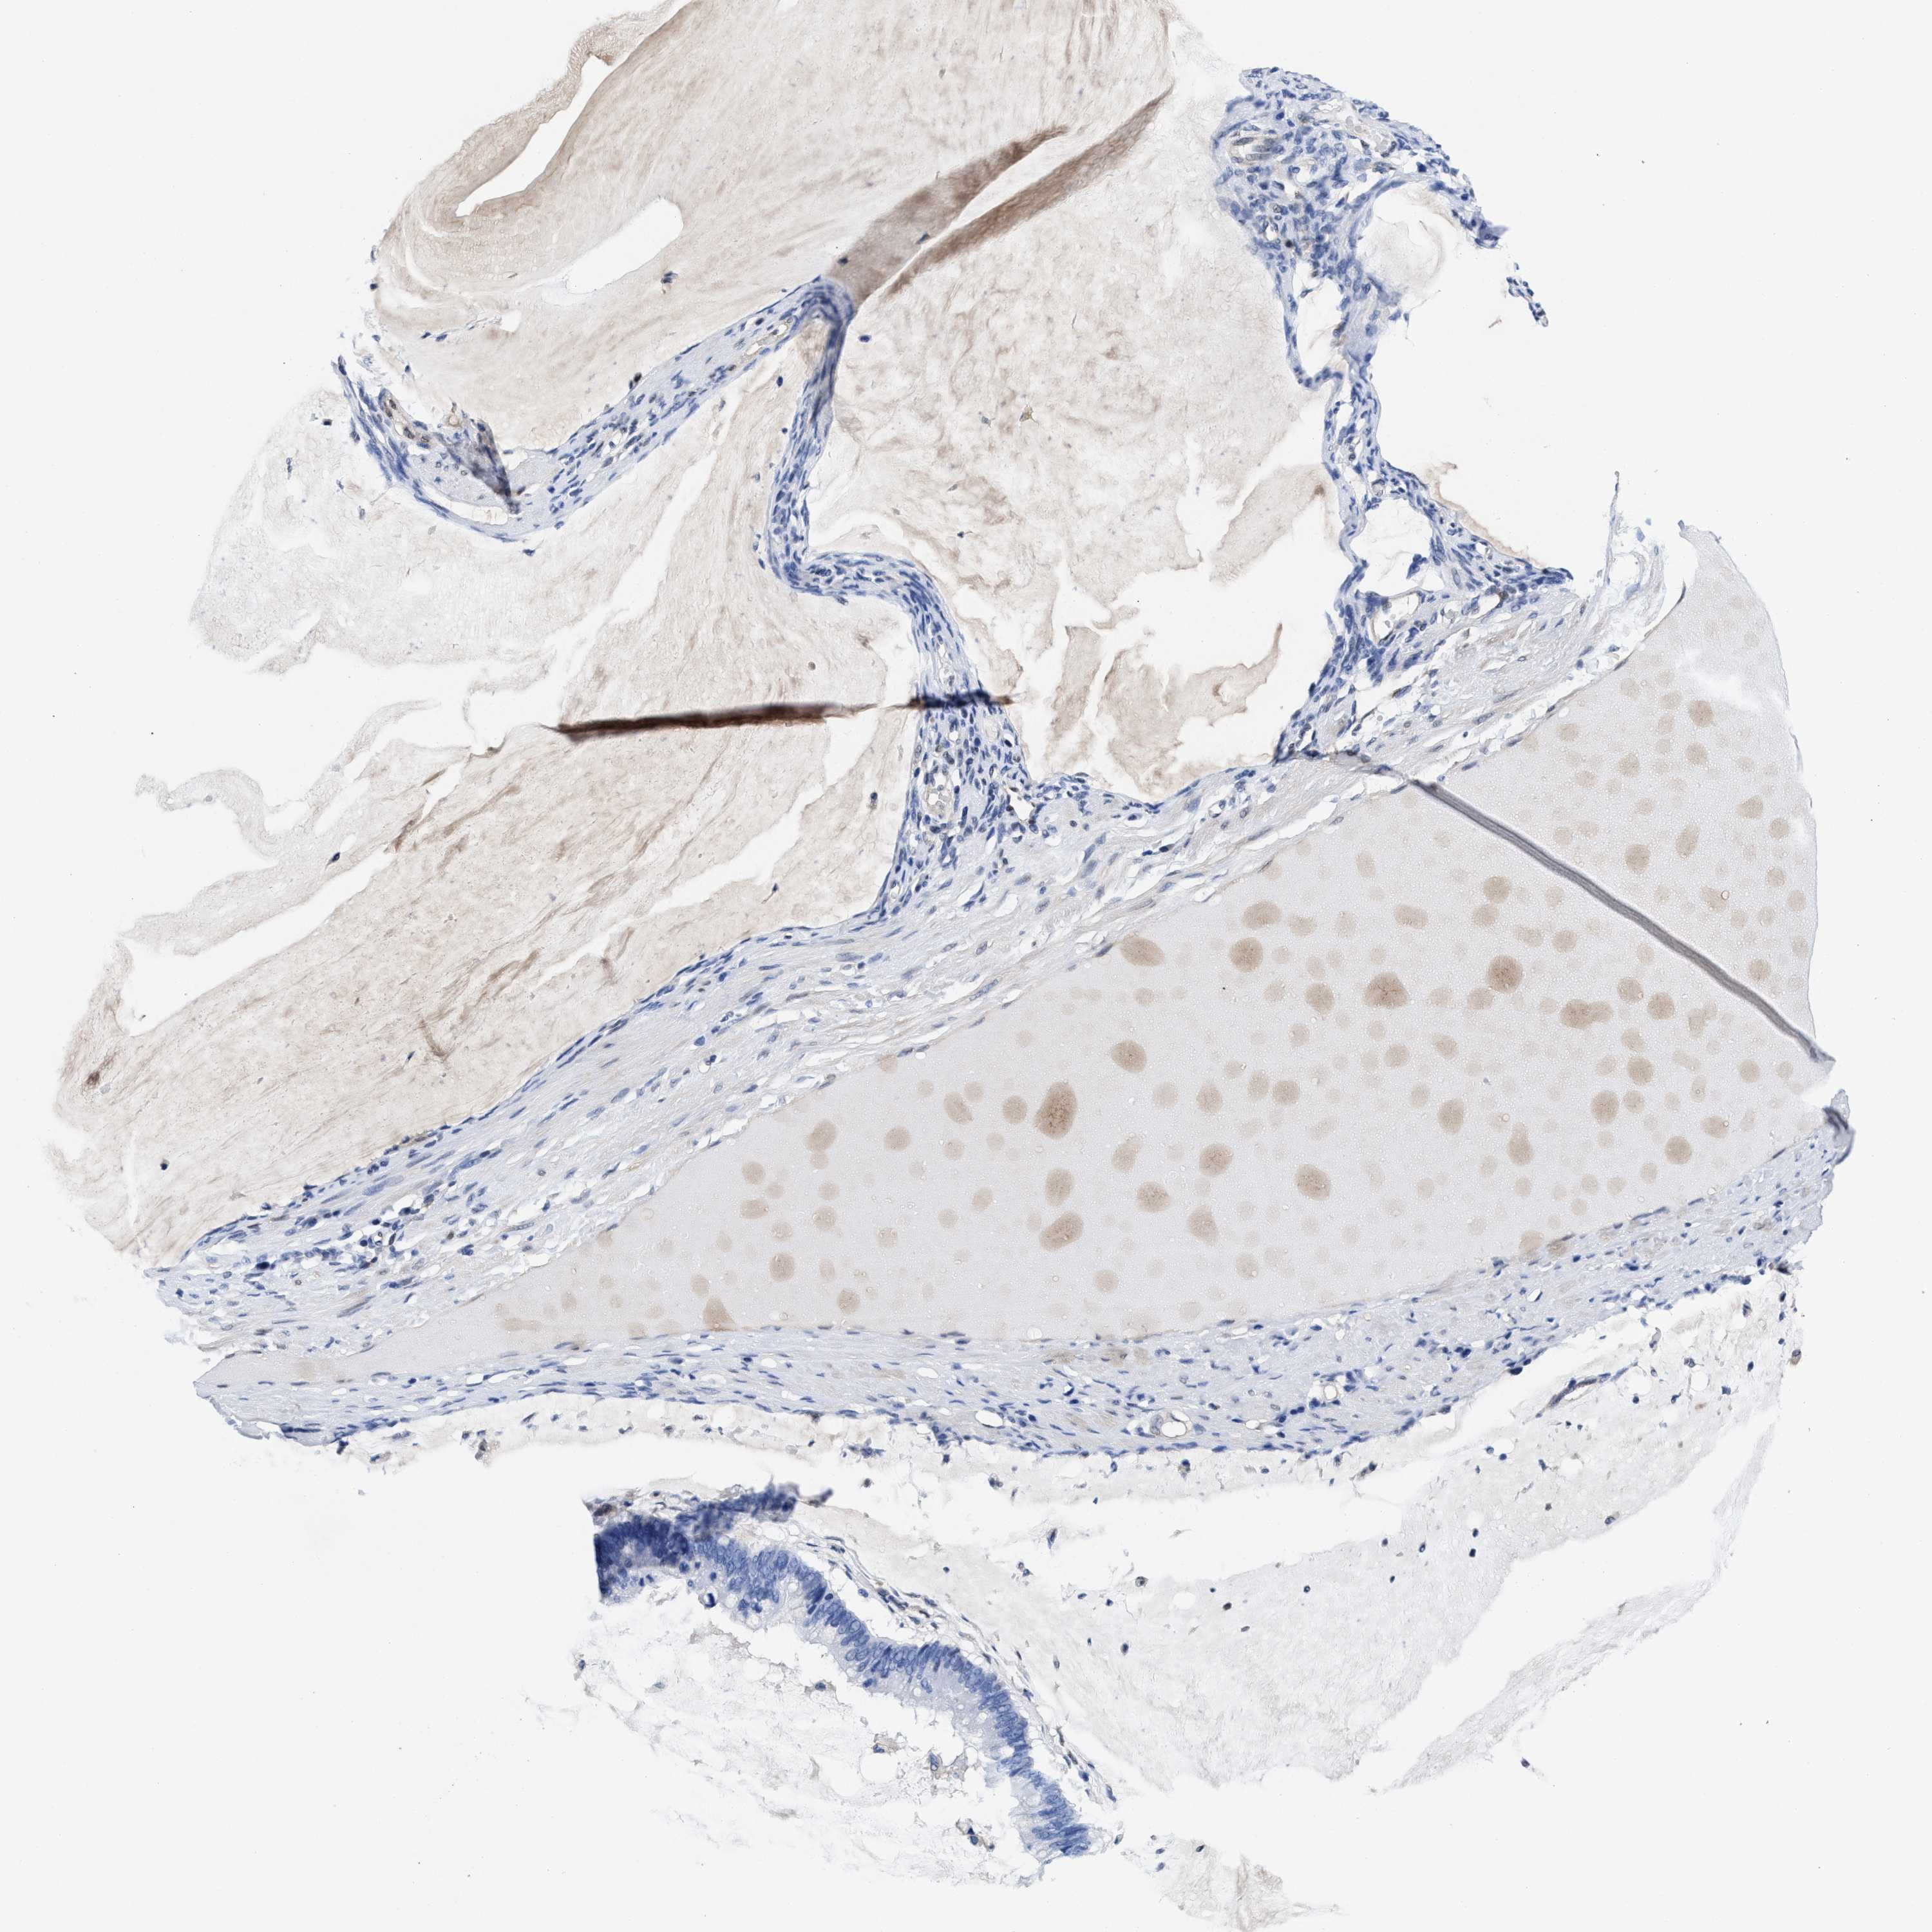

OVARIAN CANCER - Protein expressioni

A mouse-over function shows sample information and annotation data. Click on an image to view it in a full screen mode. Samples can be filtered based on level of antibody staining by selecting one or several of the following categories: high, medium, low and not detected. The assay and annotation is described here.

Note that samples used for immunohistochemistry by the Human Protein Atlas do not correspond to samples in the TCGA dataset.

Antibody stainingi

Antibody staining in the annotated cell types in the current human tissue is reported as not detected, low, medium, or high, based on conventional immunohistochemistry profiling in selected tissues. This score is based on the combination of the staining intensity and fraction of stained cells.

Each image is clickable and will lead to virtual microscopy that enables deeper exploration of all samples and also displays staining intensity scores, fraction scores and subcellular localization as well as patient and tissue information for each sample.

HPA022434

HPA022953

HPA022959

HPA028758

CAB007783

Staining

Cystadenocarcinoma, serous, NOS

Carcinoma, endometroid

Cystadenocarcinoma, mucinous, NOS

Carcinoma, NOS